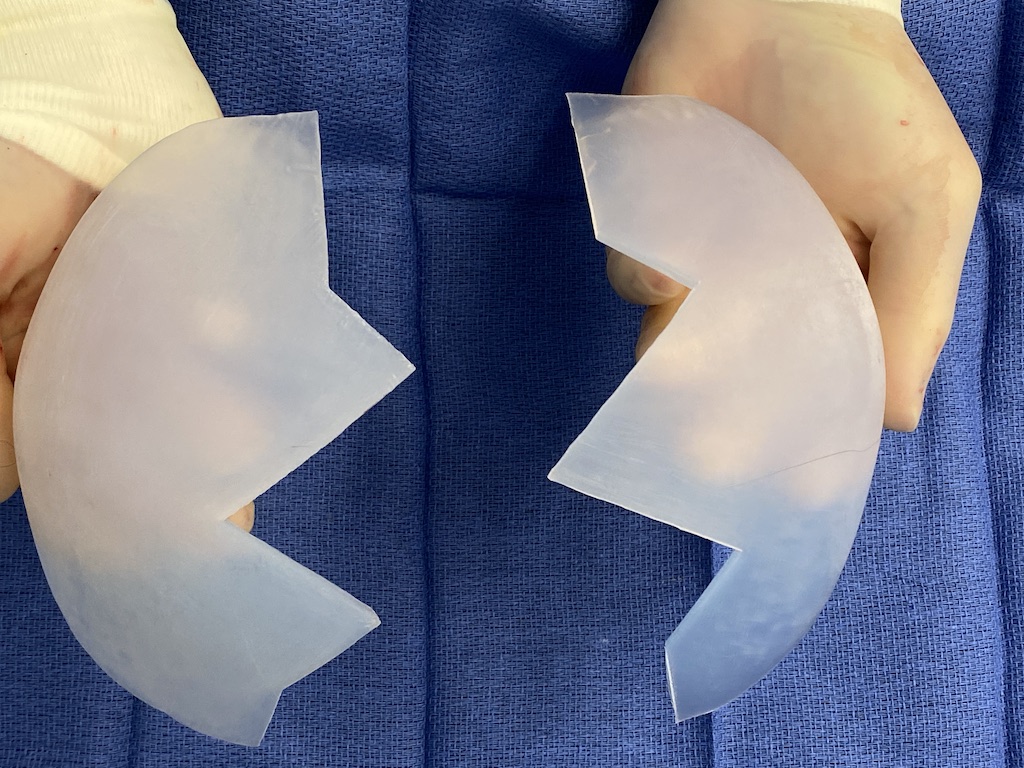

Desire for major head reshaping with a taler and wider head shape.

Placement of large two piece custom skull implant through a sagittal scalp incision.

Desire for major head reshaping with a taler and wider head shape.

Placement of large two piece custom skull implant through a sagittal scalp incision.